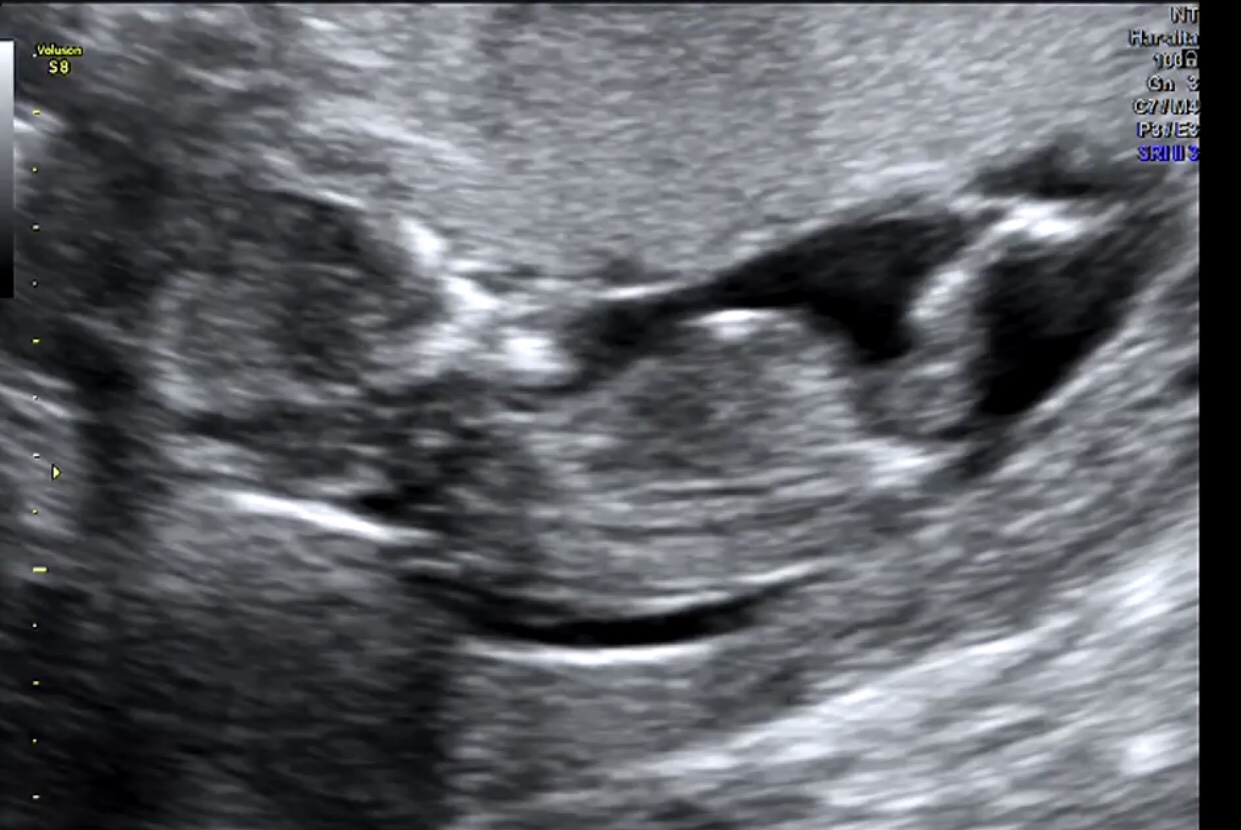

Not the best photos but if it's the nub I see in the bottom pic I'm thinking it looks girlie

That bottom pic seems to show a very girly nub ;)